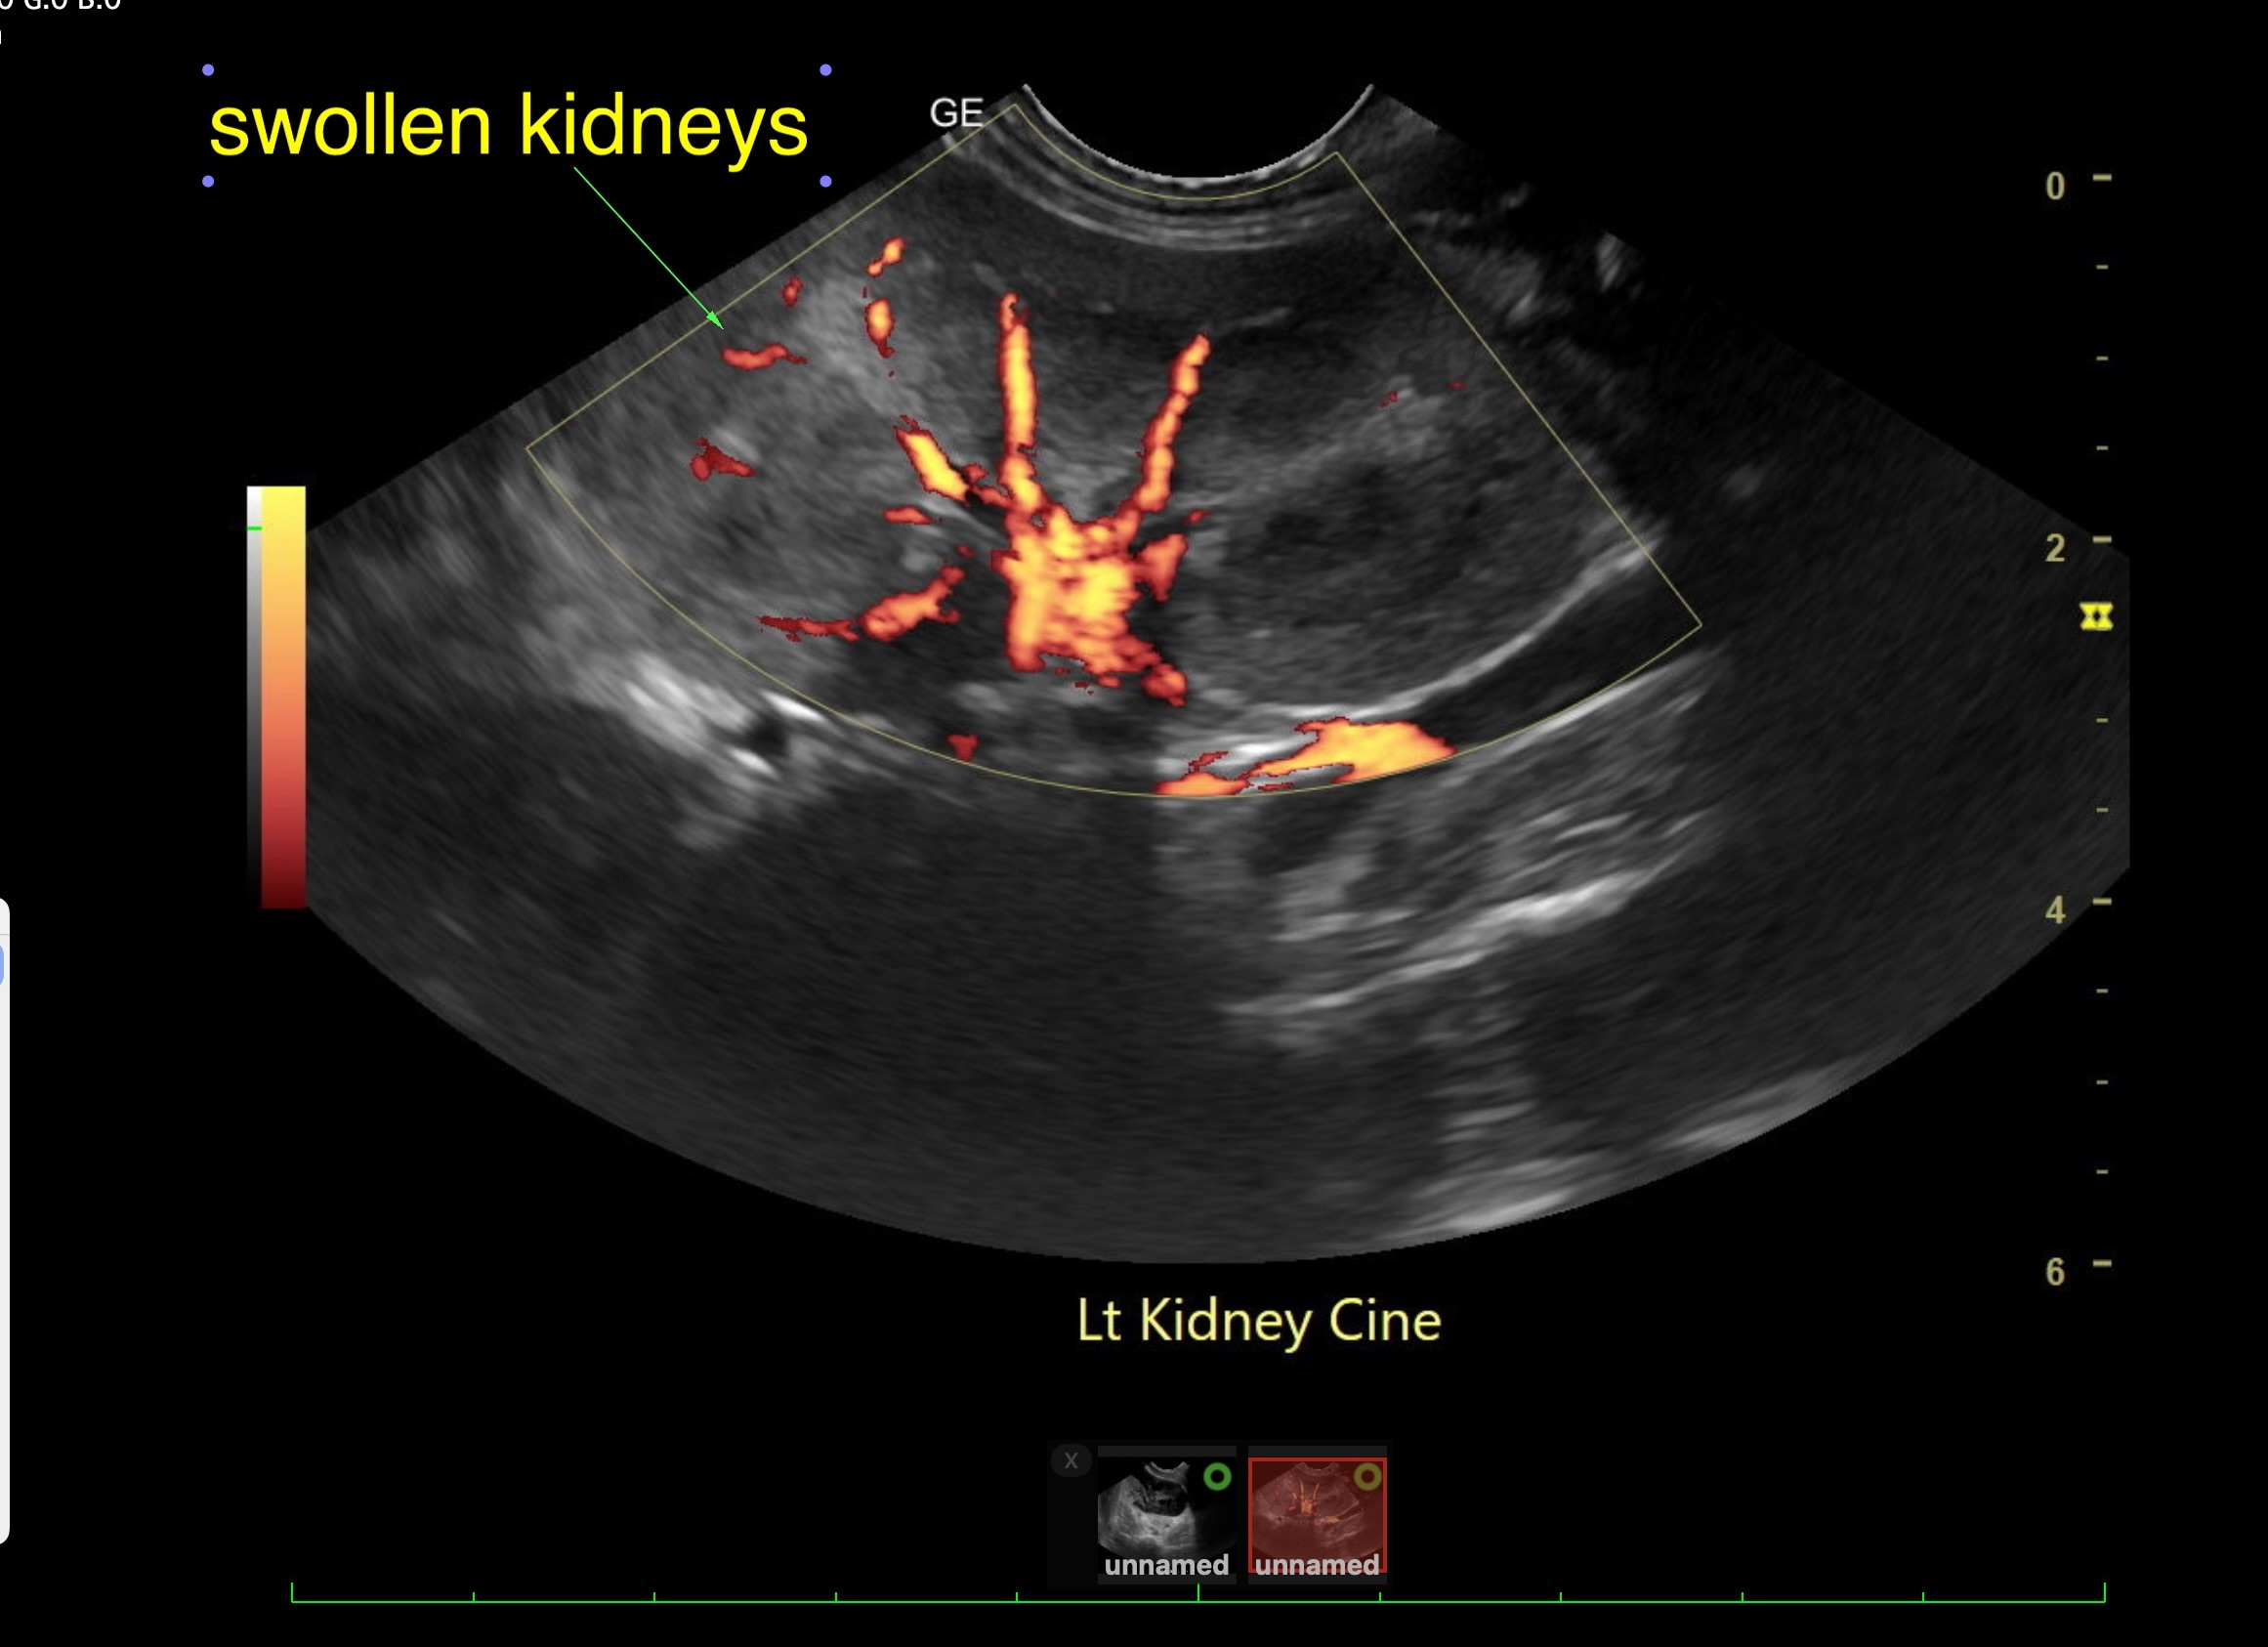

Labwork (fasted): TP 4.5, Alb 2.5, ALP 144, ALT 155, GGT 3, Bili 0.4, Cre 0.3, Cho 51, Amy 266 CBC – HCT 39%, Hgb 12.0 UA – USG 1.030pH 6, 1+ bilirubin, WBC 4-10/hpf, rods 26-50/hpf Negative Accuplex Bile Acids: Pre 299.2, Post-meal – 90.7